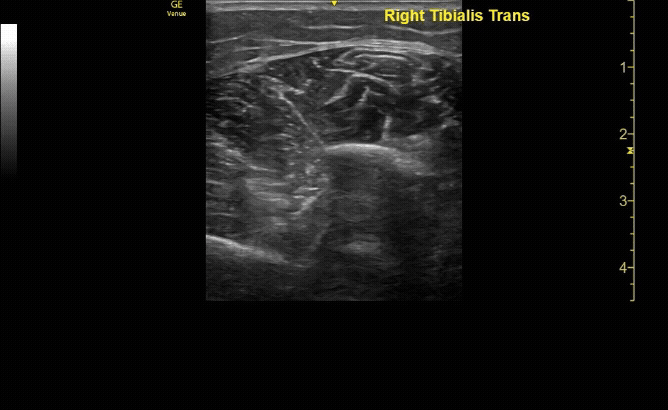

Affected tibia in transverse view.

c/o Santiago Tovar, MD